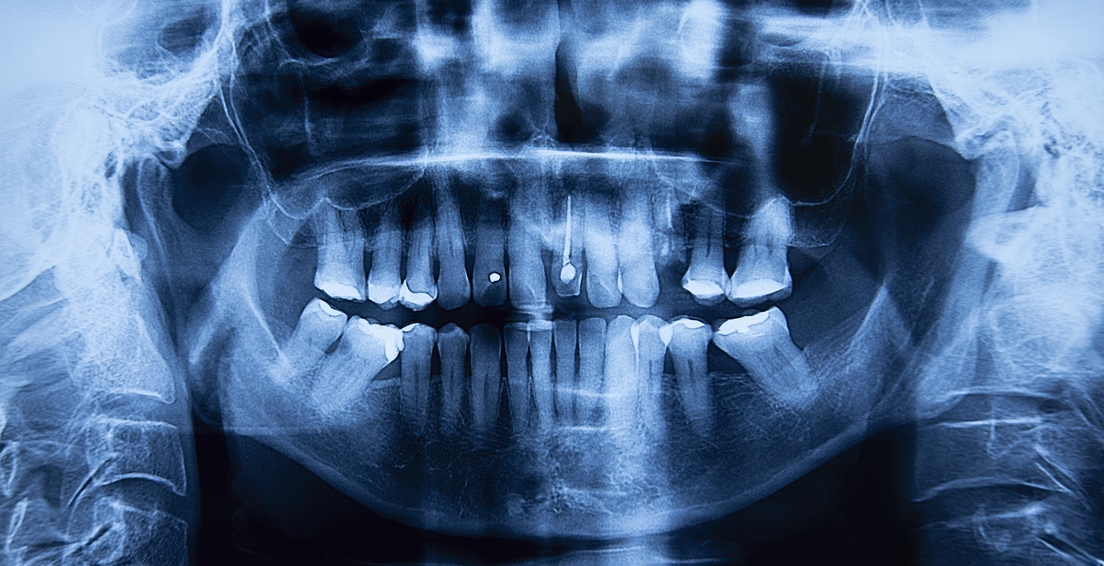

En una etapa avanzada, la maloclusión puede provocar dolor en la zona de los músculos masticatorios (responsables de los movimientos de la mandíbula) y disfunción de la articulación temporomandibular (ATM), principal conexión entre el cráneo y la mandíbula que asegura su apertura y cierre. Por tanto, puede provocar problemas para masticar o dolores de cabeza, explica Vladislav Nikitin, profesor de la Universidad Politécnica Nacional de Investigación de Perm (Rusia).

La ortodoncia es uno de los tratamientos más comunes en caso de una mordida imperfecta. Hoy en día, las opciones, tanto en materiales como en métodos, son más diversas que en el pasado y dependen del tipo y gravedad de la maloclusión, así como de otros factores individuales. Los apliques dentales o 'brackets', así como los alineadores, son una solución de eficacia comprobada. Ambos ejercen una presión gradual sobre los dientes, moviéndolos hacia una posición adecuada.

Estas opciones no son las únicas y se centran principalmente en la alineación dental, no en la posición de la mandíbula. En ese caso, podría requerirse de procedimientos quirúrgicos que impliquen la reposición quirúrgica de la mandíbula. "También pueden realizarse procedimientos periodontales o restaurativos para corregir problemas de encías o dientes que estén afectando la mordida", indica la clínica dental española Cristina Viyuela.